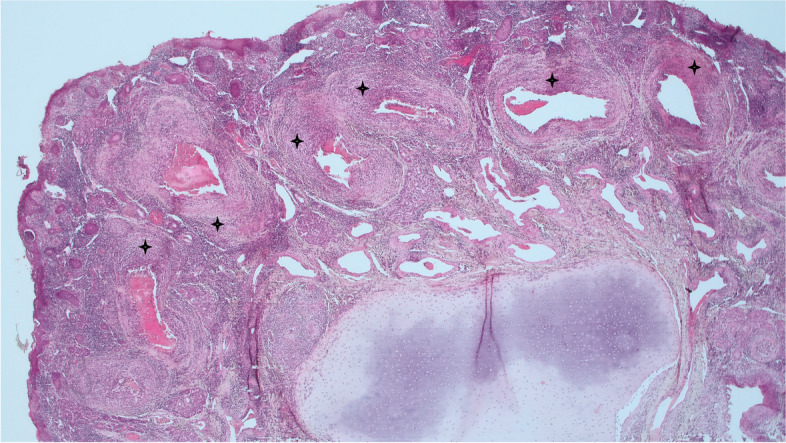

Case presentation: Using similar methods this case study reports on the findings of the first reported cases in an Irish Flock of MCF- like systemic necrotizing vasculitis in sheep associated with OvHV-2. Sheep A, a 16-month-old Texel-cross hogget displayed signs of ill- thrift, Sheep B, a nine-month-old Belclare-cross lamb, was found dead having displayed no obvious symptoms. Both cases occurred on the same farm, however the animals were not related. Lymphohistiocytic vasculitis of various tissues was the predominant histopathological finding in both animals.